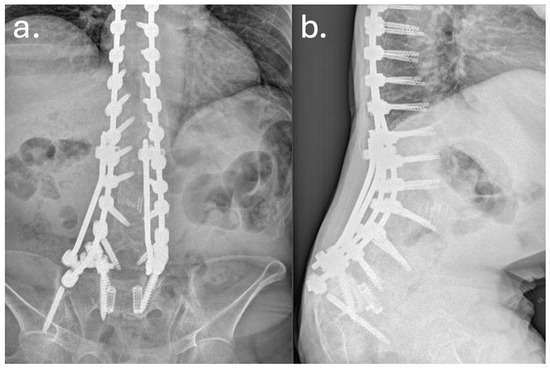

In December 2019, a revision surgery was performed due to partial construct failure and suspected iliac screw loosening as showed in Figure 4 and Figure 5. The left iliac screw and bilateral screws at T4–T5 were removed. New pedicle screws were placed bilaterally at T2–T3, and two additional rods were added, creating a delta-rod four-rod configuration to enhance construct stability and distribute stress.

Figure 5. Anteroposterior (a) and lateral (b) radiographs at 2-year follow-up. The images demonstrate loosening of the bilateral iliac screws with peri-implant radiolucency, consistent with mechanical failure at the lumbopelvic junction. The sagittal view shows partial loss of the achieved lumbar lordosis and persistent sagittal imbalance, suggesting progressive biomechanical compromise of the construct despite maintenance of overall instrumentation continuity.